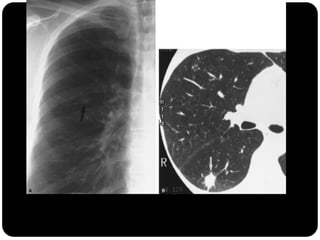

Pequeno nódulo no pulmão direito

Nódulos

 O nódulo pulmonar é uma lesão arredondada ou ovalada, de

limites parcialmente precisos, com menos de 3 cm de

diâmetro.